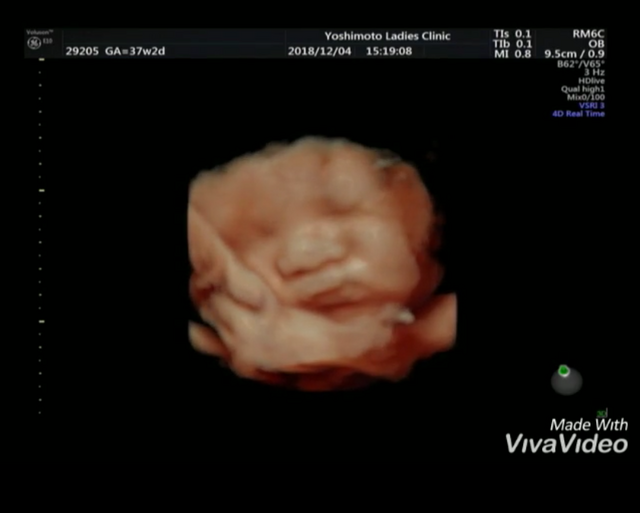

出産前の最後の妊婦健診。 いつもはママ1人で病院へ行き、いつもエコーで顔を隠して見せてくれず… 。

最後の妊婦健診はパパも一緒に行ったらサービス精神旺盛なのかアップでバッチリ顔を見せてくれました‼ ちゃっかり舌も出しちゃって(笑) 産まれた今では大切な大切な宝物です★